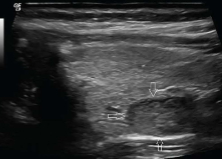

This nodule within the right lobe of the thyroid most likely represents:

Follicular adenoma

Which ultrasound finding is most characteristic of a follicular adenoma?

Hypoechoic peripheral halo caused by a complete fibrous capsule